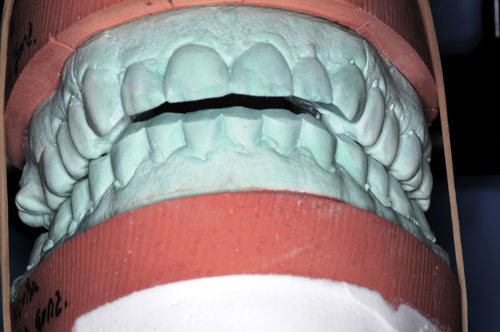

ESTUDIO ESTÁTICO DE LOS MODELOS PREVIOS A LA PRIMERA REHABILITACIÓN APORTADOS POR LA ENFERMA:Modelos Color Blanco

B- ESTUDIO ESTÁTICO DE LOS MODELOS PREVIOS A LA 1ª REHABILITACIÓN APORTADOS POR LA ENFERMA: (La situación oclusal que la enferma tenía antes de que la tocara un dentista (MODELOS COLOR BLANCO)

ESTUDIO ESTÁTICO Y CINEMÁTICO DE LA OCLUSIÓN PRESENTE: Modelos Color Verde

Diferencias entre ambos modelos:

A nivel de segundos molares= 4 mm +

A nivel de primeros molares= 3,50 mm +

A nivel de incisivo central=5,50 mm +

Antes de la 1ª intervención, los segundos molares superior e inferior derechos tocaban.